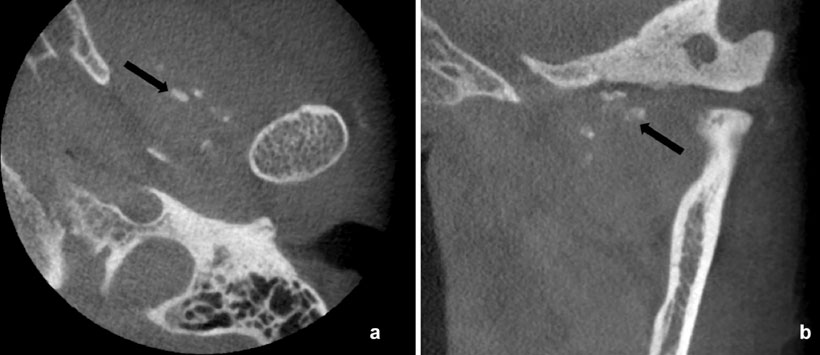

Caso 1: Mujer de 60 años fue remitida con motivo principal de incomodidad durante la masticación durante 3 años. El examen físico mostró asimetría facial y una ligera desviación de la línea media de la mandíbula hacia el lado izquierdo. También presentó sensibilidad en el área derecha de la ATM (Figura 1, 2 y 3).

Figura 2: Tomografía Computarizada (TC) revelaron hiperplasia y esclerosis de la región anterior del cóndilo (flechas negras) y un cuerpo calcificado (flecha blanca) en los cortes axiales (a) y coronales (b)

Figura 3: Tomografía Computarizada (TC) en el que se observa ensanchamiento del espacio articular (flecha negra) en la ATM derecha (a) en comparación con la ATM izquierda (b)